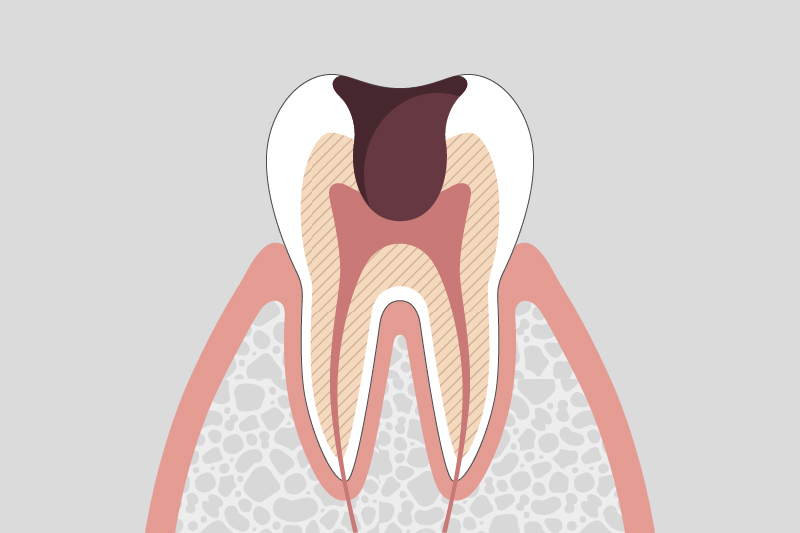

C3.

神経まで進行した虫歯

強い痛みが発生し、神経の治療が必要になる。